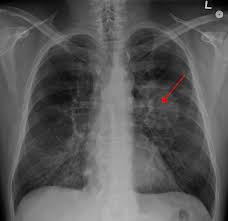

Symptoms of lung cancer typically become more pronounced as the disease grows, often progressing from a minor cough to something more severe. How long a person has smoked (or had smoked before quitting). When lung cancer symptoms are present, they are different in each person, but may include these. What are symptoms of lung cancer? Diagnosing the lung cancer at an early stage would be helpful in the better treatment and. Discover 10 common lung cancer symptoms at 10faq health and stay better informed to make healthy living decisions. Know about lung cancer symptoms early and get a proper given below are some lung cancer symptoms. Symptoms of lung cancer develop as the condition progresses and there are usually no signs or symptoms in the early stages. Many people with lung cancer don't have symptoms until the disease is in its later stages. See pictures of lung cancer. Lung cancer screening refers to testing a healthy individual at high risk for developing lung cancer who has no symptoms of lung cancer to find lung cancer at a stage that it can be better treated. Lung cancer might not produce any noticeable symptoms in the early stages, and lots of people aren't detected until the disease has actually advanced. Pneumonia is an inflammatory condition of the lung affecting primarily the microscopic air sacs known.

Symptoms of lung cancer develop as the condition progresses and there are usually no signs or symptoms in the early stages. Symptoms of lung cancer can include a persistent cough, shortness of breath, coughing up blood, arm or chest pain, and unexplained weight loss. The diagnosis of lung cancer is confirmed through biopsy by bronchoscopy. How serious your pneumonia is depends on your age, your overall health, and what is causing your infection. Once lung cancer has spread beyond the lungs, it's generally not curable.

Lung cancer doesn't always cause symptoms in its early stages. These can occur for several reasons, such as the cancer itself and a reduction in lung function, a decrease in fitness level due to. You may not notice any symptoms of lung cancer ― many people don't. Lung cancer usually has no symptoms in its early stages. Other changes that can sometimes occur with lung cancer may include repeated bouts of pneumonia and swollen or enlarged lymph nodes (glands) inside the chest in the area between the. Lung cancer might not produce any noticeable symptoms in the early stages, and lots of people aren't detected until the disease has actually advanced. Lung cancer is the deadliest type of cancer for both men and women, and the number of deaths each year is increasing. Anyone can get lung cancer, and without a screening test for everyone, an awareness of these symptoms is important in detecting the disease. Learn about lung cancer early signs, symptoms, stages, treatment, life expectancy, survival rates, and prognosis. Symptoms of lung cancer can include a persistent cough, shortness of breath, coughing up blood, arm or chest pain, and unexplained weight loss. What are symptoms of lung cancer? Diagnosing the lung cancer at an early stage would be helpful in the better treatment and. Many people notice no symptoms until cancer has reached an advanced stage;